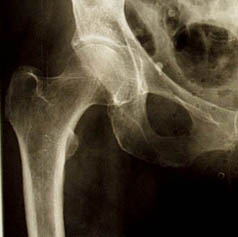

Een DHS wordt geplaatst bij een bepaald type “gebroken heupen”, wanneer het dijbeen (femur) breekt op het brede deel vlak voor de dijbeenhals (collum).

Men spreekt dan van een subtrochantere femurfractuur. De DHS of dynamic hip screw bestaat in feite uit twee componenten.We onderscheiden een stevige schroef die vanuit de laterale cortex van de schacht in de kop grijpt en een plaat die op de schroef aangrijpt en het geheel aan de schacht fixeert.